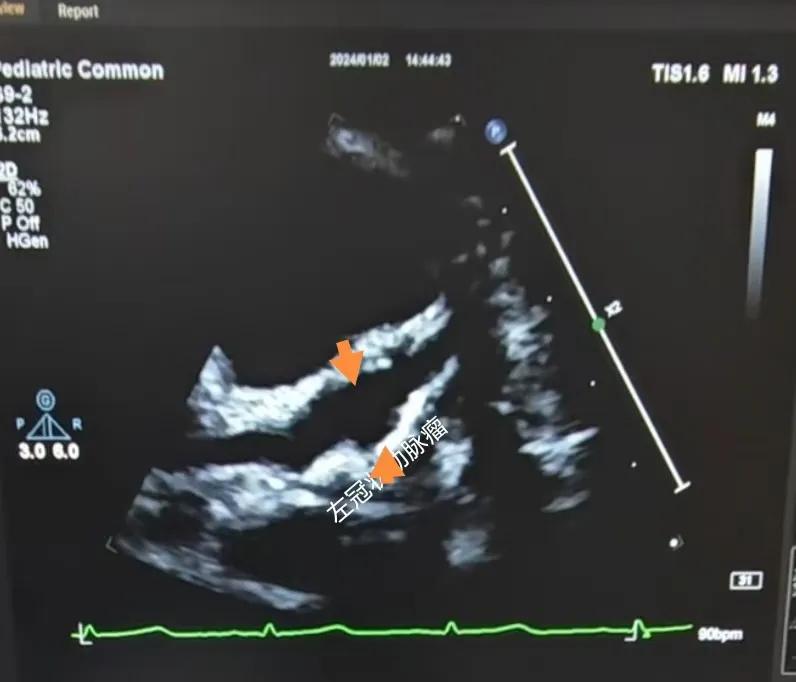

(川崎病患兒:左冠狀動(dòng)脈瘤)